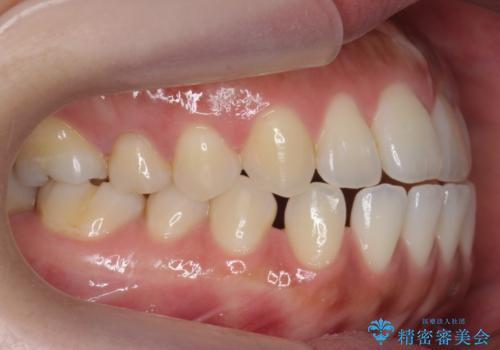

受け口、すきっ歯を インビザラインで モニター治療

- 前歯のすき間と受け口を気にして来院。

マウスピースでしっかり閉じています。

下の前歯を後方に移動するため、ゴムを上下のマウスピースにかけてもらいました。